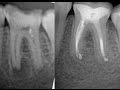

Одним из методов восстановления десен является хирургическая коррекция. В ходе операции, специалист сглаживает поверхность кости и прилегающих тканей, делает разрезы для формирования нового положения десны и при необходимости проводит трансплантацию десневого лоскута.